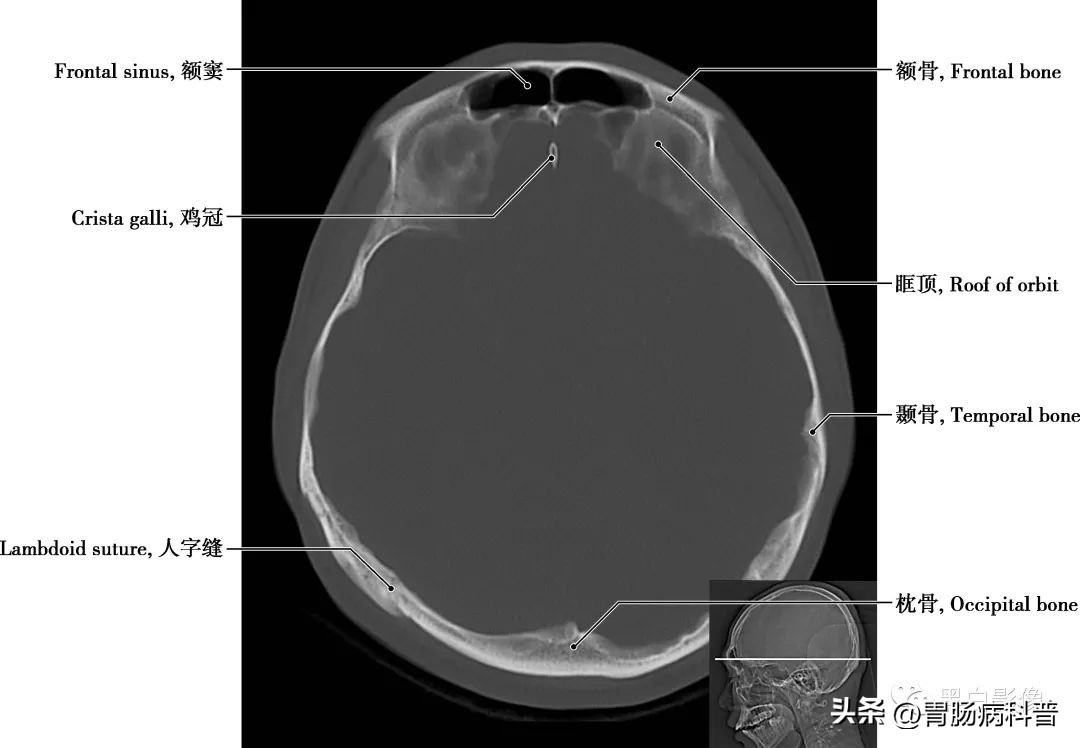

图1-2-11 经大脑脚轴位切面

眶顶 即眶上壁,前部为额骨水平板,后部为蝶骨小翼。鸡冠 筛板的前份向上伸出的骨嵴